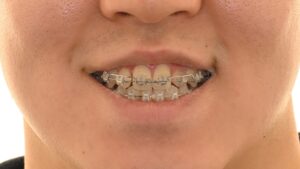

망우동 치과 정중선 편위 및 삐뚤어진 치열, 가지런한 배열을 회복하기 위한 발치 교정

안녕하세요 망우동 치과 김정은 원장입니다. 치아가 삐뚤어 교정 상담을 받게 되면 많은 분들이먼저 궁금해하시는 것이 바로 비발치 인지 발치 교정인지에 대한 부분입니다. 23.07.18 가능하다면 치아를 뽑지않고 배열만 정리하는 비발치 방식을…